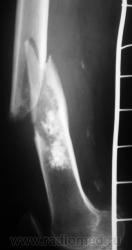

Ну, и, после "репозиции".

н\3 бедра со смещением по длине и ширине. Отломки находятся под углом открытым кпереди прим. в 10-15 град.

А не создается-ли впечатления, что представленный перелом патологический? Первый снимок произведен через час после травмы.

костных структур в проекции прелома, то действительно это патологический перелом. Честно не сразу обратил внимание.

Что это - не скажу (под рукой нет литературы). Но. 1.Процесс опухолевый - в средней части, по заднему контуру отмечается вздутие кости. 2.Относительно длительно текущий - вздутие достаточно протяженное. 3.Пока еще относительно доброкачественный - кортикальный слой созранен. 4. Многоузловой (мультифокальный) - не менее 3-х узлов/фокусов. В зависимости от возраста/пола/анамнеза вполне может быть метастатическим. 5.Перелом все-таки патологический - линия перелома проходит через верхнюю часть патологического субстрата.

Это может оказаться и безобидным обызвествлением костного мозга после инфаркта, хондромой или хондросаркомой. - Уроки Татьяны Валентиновны. Но вздутия не вижу - его в боковой проекции симулирует третий фрагмент в месте перелома. Ну а метастаз - маловероятен... Опять же - "горим" на сочетанной патологии...

Как по мне, так там наоборот, локальное (хотя и на достаточном протяжении) УТОЛЩЕНИЕ кортикального слоя по задней поверхности, хотя и в сочетании с умеренным вздутием.